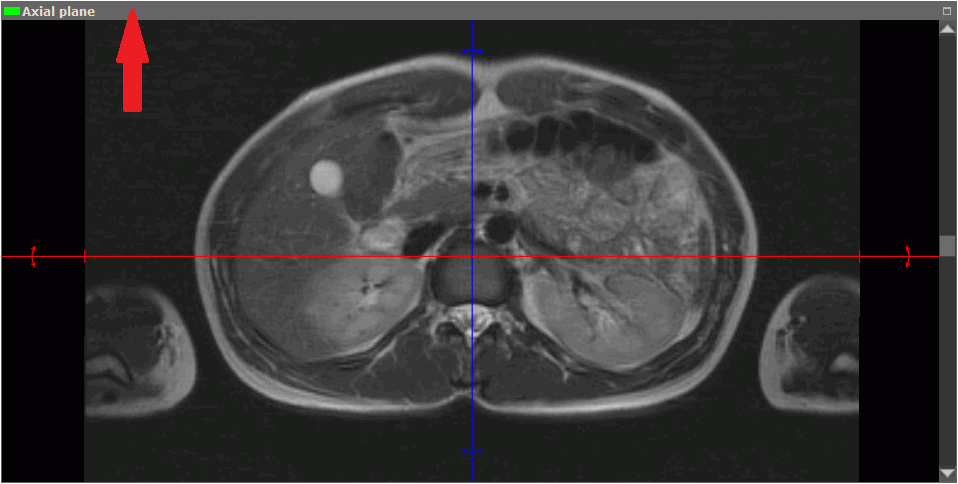

1. Activate the window in which the target image is located. To do this, click the left mouse button on the window area or header (marked by the arrow in Fig. 5.25).